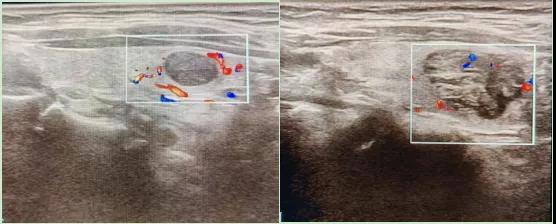

二、彩超如何“揪出”甲狀腺瘤?

彩超是一種無(wú)創(chuàng)、無(wú)輻射的檢查手段,被譽(yù)為甲狀腺的“高清攝像頭”。它的原理是:

超聲波探測(cè):通過發(fā)射高頻聲波,生成甲狀腺的實(shí)時(shí)圖像。

彩色血流顯示:用紅藍(lán)色標(biāo)記血流信號(hào),區(qū)分腫瘤的供血情況。

1.形態(tài):良性多呈圓形,邊界清晰;惡性可能不規(guī)則、邊緣模糊。

2.回聲:低回聲結(jié)節(jié)風(fēng)險(xiǎn)較高(像“烏云”一樣暗)。

3.鈣化:細(xì)小砂礫樣鈣化提示惡性可能。

4.血流信號(hào):惡性結(jié)節(jié)常有豐富紊亂的血流。